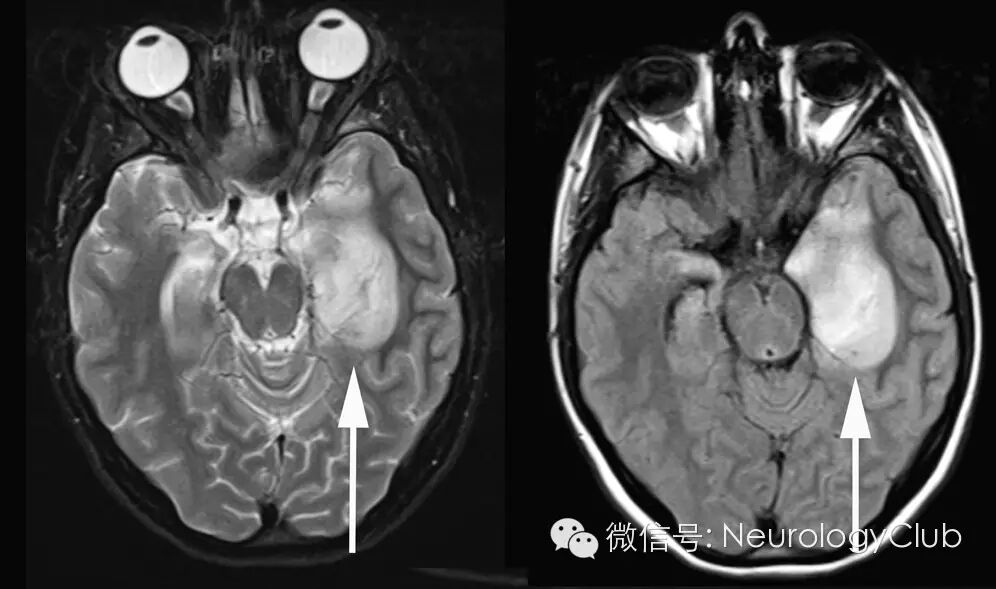

图3:磁共振T2WI/FLAIR提示颞叶脑实质水肿,瘀点状出血(混杂信号)